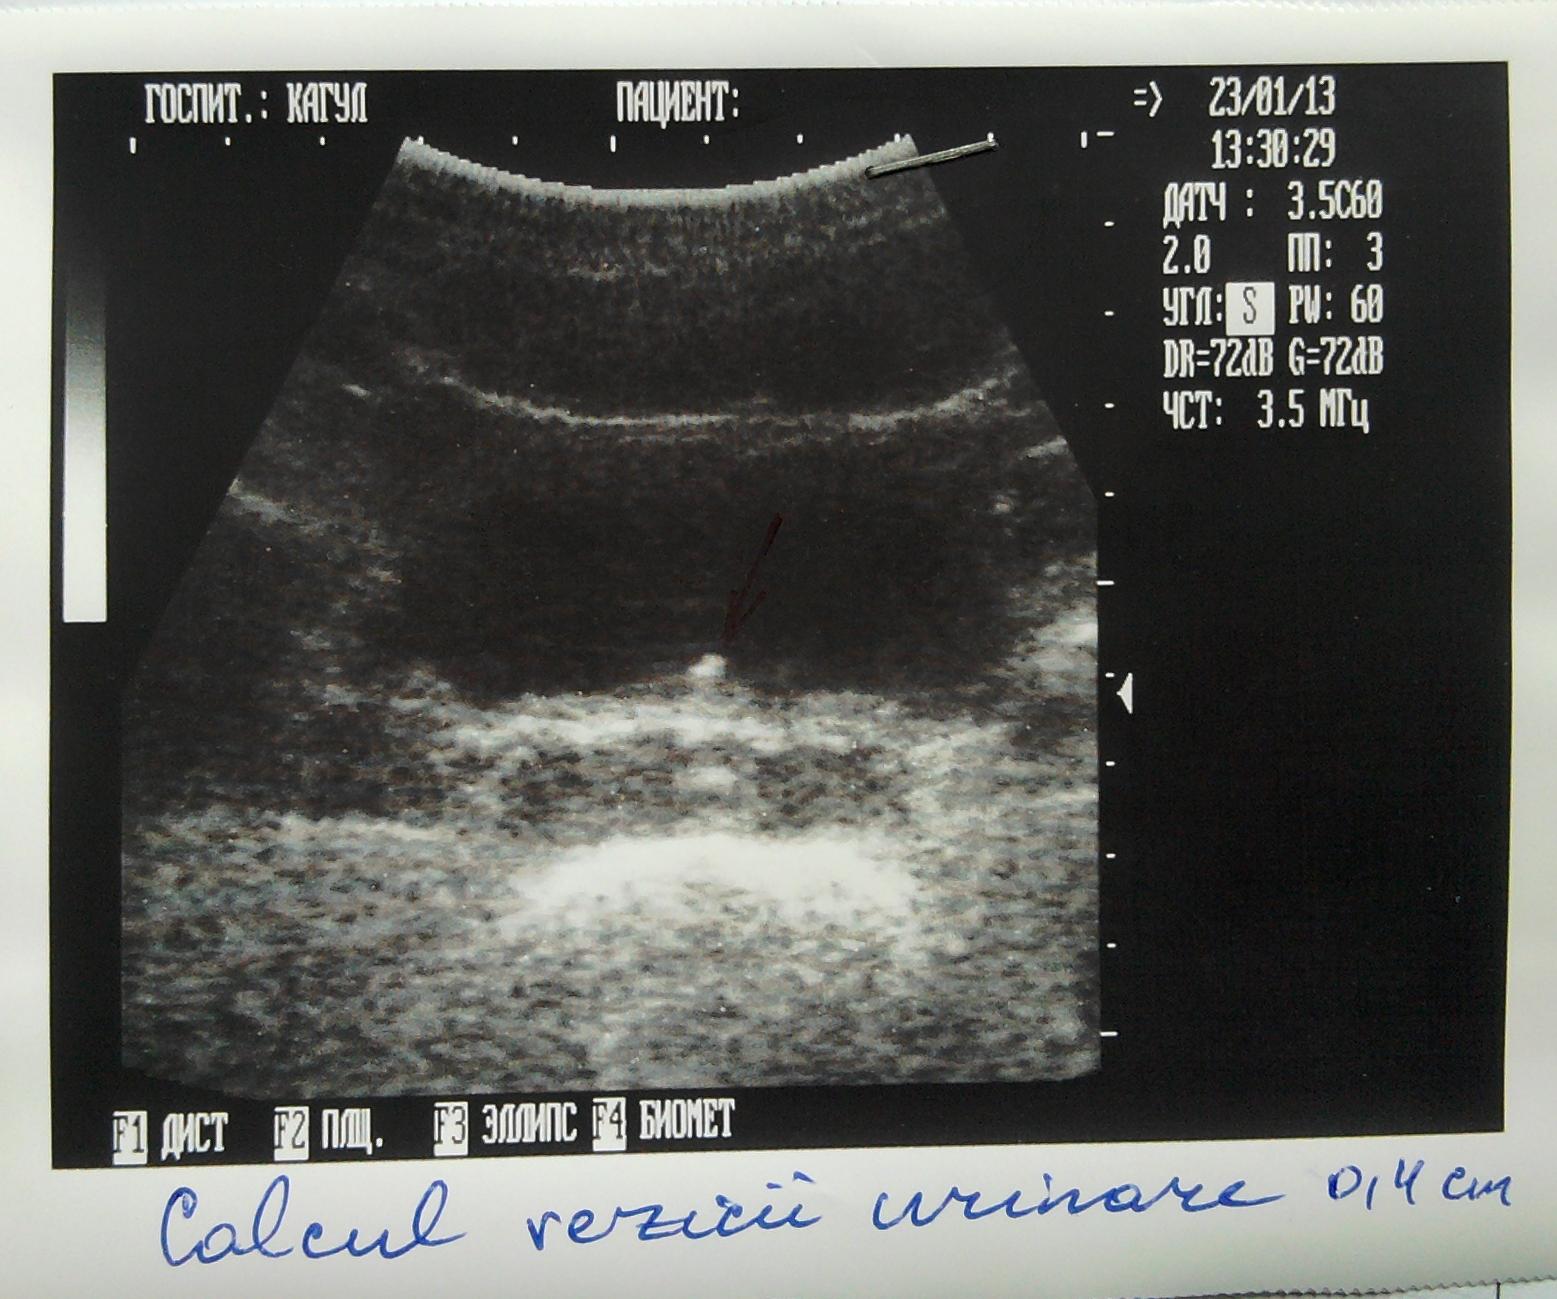

Здравствуйте я зделал год назад узи мочевого пузыря и у меня обнаружили камушек размером в 0,4 см, потом я посетил местного уролога он назначил мне Шилинтонг по 3 таблетки 3 раза в день. Я иногда по 4 пил.

- Через пол года я опять зделал узи и камушек как стоял так и стоит, после этого я пошол к врачу он решил что они видят не камушик а что-то с простатой и взял анализ( анализ нормальный как он мне сказал ) и сказал что это наверное кальцинат и не надо не какого личения. Чтоб я опять через пол года зделал узи.

Ниже я прикрепил фото узи.